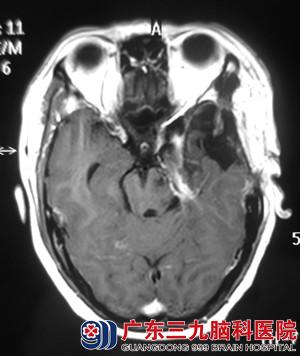

芳姐十二年前被诊断为“颅内胆脂瘤”,在当地医院行手术治疗,但术后遗留下左侧面部麻木、左侧眼球外展障碍,视物重影及左下肢运动欠佳。去年8月开始出现发作性左侧面部、眼睑抽搐,一周前加重,到我院行头颅MR提示:左侧中后颅窝占位性病变,考虑胆脂瘤复发。

当看到检查结果时,芳姐一股恐惧感油然而生,经再三考虑决定在三九脑科医院接受手术治疗。入院时查体:患者左侧眼球结膜稍充血,外视及上视障碍,左侧面部麻木,左侧面部肌肉萎缩。完善相关检查后,由综合神经外科的鲁明主任主刀,在全麻下行硬脑膜外入路左侧中后颅窝复发胆脂瘤切除术,术中显微镜下见黄白色肿瘤组织,质地疏松,无血供,考虑为胆脂瘤复发,予肿瘤切除,修补颅底,手术顺利结束。术后芳姐经过专科治疗,术前症状均明显较术前好转,十天后芳姐康复出院。术后病理结果:胆脂瘤。

术前 ?xml:namespace>